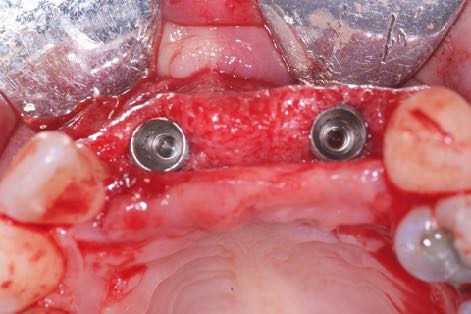

La stabilité secondaire désigne en revanche la stabilité biologique, ou ostéo-intégration. C’est elle qui détermine, en dernier lieu, la capacité de la restauration implanto-portée à supporter les forces fonctionnelles et à jouer un rôle pleinement fonctionnel dans la dentition d’un patient.

Il faudrait se concentrer sur la stabilité secondaire et l’obtenir le plus vite possible, en préservant en même temps la viabilité et la stabilité de l’os péri-implantaire, pour assurer la réussite clinique de l'implant à long terme.

Dr Stephen Jacobs : La stabilité secondaire c’est l’ostéo-intégration, et c’est assurément notre objectif ultime. Idéalement, le but est d’obtenir une stabilité secondaire suffisante le plus rapidement possible pour restaurer chez nos patients une fonction normale avec leurs restaurations des couronnes implanto-portées.

Je suis convaincu que le maintien de l’os marginal péri-implantaire est l’un des facteurs clés de prévention des complications biologiques futures. Par conséquent, si l'on arrive à obtenir une stabilité secondaire en minimisant les lésions osseuses au niveau cellulaire, les conditions d’une réussite prévisible durable sont presque entièrement remplies.